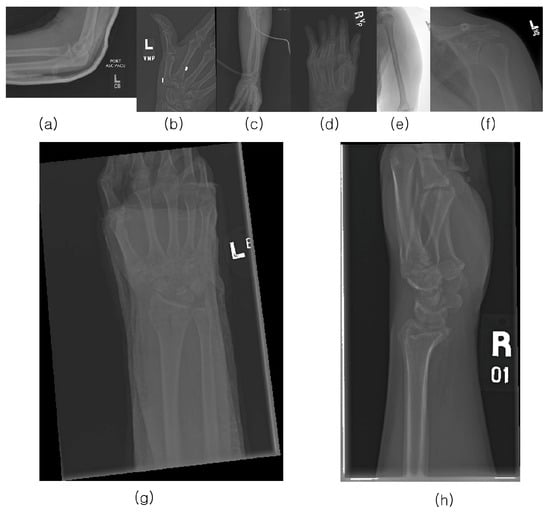

3. Materials

The musculoskeletal radiographs (MURA) dataset is a large compilation of musculoskeletal radiographs for seven upper extremities: the elbow, finger, forearm, hand, humerus, shoulder, and wrist. These were obtained from 12,173 patients at Stanford Hospital between 2001 and 2012 and were manually classified as normal or abnormal by Stanford Hospital radiologists. The total number of images is 40,561, of which 9752 (negative: 5765, positive: 3987) are wrist images. In addition, the validation dataset comprises 659 images (negative: 364, positive: 259). Stanford University has released the MURA dataset for research purposes. Figure 1 provides examples from the positive dataset.

Figure 1. Positive MURA dataset: (a) elbow, (b) finger, (c) forearm, (d) hand, (e) humerus, (f) shoulder, (g) wrist, (h) wrist.